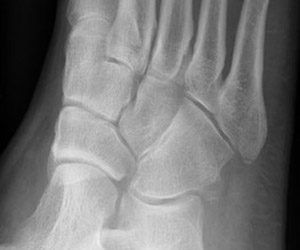

Skeletal Trauma > Foot & Heel > Foot & Heel Quiz

What fracture is shown here?